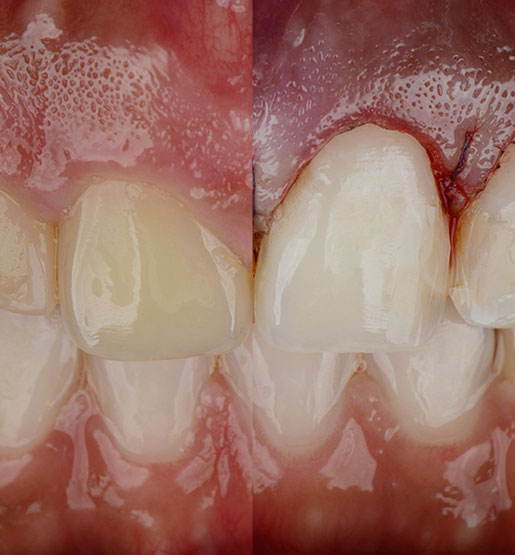

Sin embargo, la sonrisa gingival puede corregirse mediante un procedimiento llamado recontorneo estético gingival o de la encía, el cual puede realizarse por medio de una o la combinación de dos técnicas: el remodelado estético óseo y la gingivectomía.

Mediante la técnica de remodelado estético óseo se retira el exceso de encía y remodela la altura y el volumen del hueso para exponer más los dientes. Se realiza habitualmente en varios dientes para nivelar el margen de los mismos y crear una sonrisa armoniosa. Generalmente los resultados de la intervención son inmediatos y con mínimas molestias postoperatorias.

Gingivectomía

Se realiza una gingivectomía cuando se retira el exceso de encía sin necesidad de remodelar el hueso. Los resultados, al igual que el recontorneo estético gingival, son inmediatos y sin complicaciones, además de mejorar la estética de la sonrisa, mostrando el tamaño normal de los dientes al sonreír.